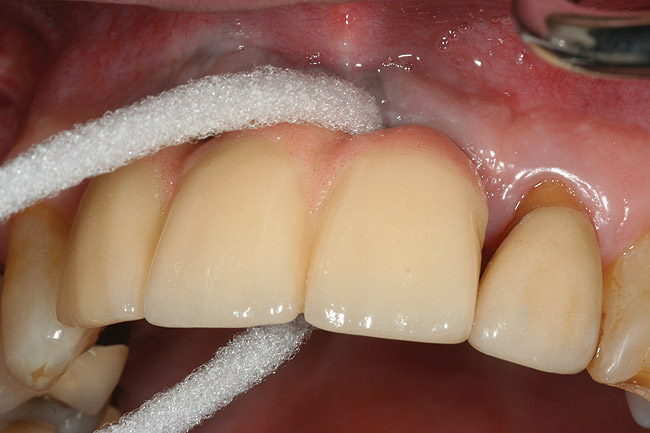

Inflammation limited to soft tissues around a dental implant may result from dental plaque colonization and is termed peri-implant mucositis. This is a reversible inflammatory condition limited to the soft tissues around the implant (without any bone loss), analogous to gingivitis around natural teeth. A diagnosis of peri-implantitis results when the inflammation spreads apically, causing progressive loss of osseointegrated supporting bone, analogous to periodontitis around natural teeth16 (Figure 2A and Figure 2B). It is essential for practitioners to be familiar with these diagnostic terms when assessing the long-term success of implants and peri-implant health (Table 1).

Figure 2a

Figureb 2  (A) Clinical and (B) radiographic views of implants at site Nos. 30 and 31 demonstrating bone loss caused by peri-implantitis after 8 years in function. Note gingival inflammation and plaque accumulation around implants.

Figure 2b